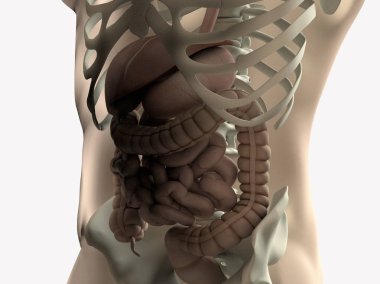

Sindirim Sistemi

En Çok Aranan Kelimeler

MaviresimlemeİnsanKadınSağlıkkanİlaçAğızSolunumerkekkalpgövdeMidebiyolojiBilimSistemözetorgİskeletanatomiKas gücübeyinSistemlersindirimGerginakciğerlerkaraciğerBöbrekiskeletOrganlaranatomikBağırsaklarBağırsakKolondolaşımdalakBenzer İçerikler